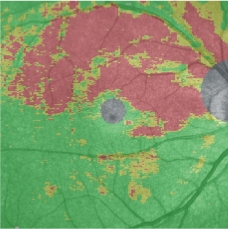

功能性多模影像

可通過將OCT的各種形態學檢查影像與NIDEK微視野視野計MP-3采集的視功能檢查數據疊加成各種功能性多模影像。